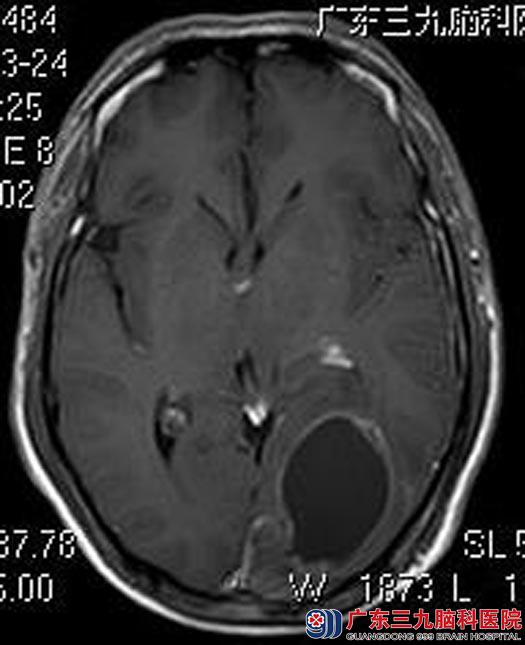

在广东三九脑科医院综合神经外科体格检查:精神食欲差,双侧瞳孔等圆等大,直径约2.5mm,对光反射灵敏,左眼视力4.7(0.5)、右眼视力4.5(0.3),双眼右侧偏盲。头颅MR检查显示:左侧顶枕部占位性病变,大小约3.8cm×6.4cm×5.9cm,考虑胶质瘤。

由鲁明主任主刀在全麻下行“左侧顶枕叶肿瘤切除术”,术中见肿瘤实质部分邻近中线,质软,呈灰白色胶样,血供较丰富,于显微镜下顺利全切除。术后谢先生的头痛头晕、恶心呕吐不适症状消失,视野较前好转,康复出院。术后病理结果提示:间变型星形细胞瘤WHO III级。